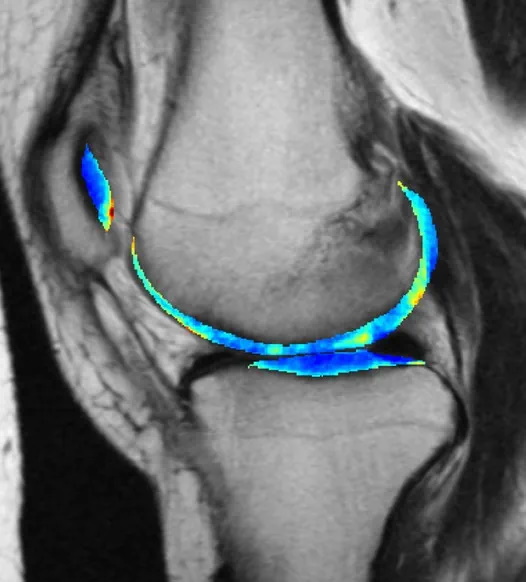

ML model detects arthritis early

One of machine learning’s most reliable use cases is training a model on a target pattern, say a particular shape or radio signal, and setting it loose on a huge body of noisy data to find possible hits that humans might struggle to perceive. This has proven useful in the medical field, where early indications of serious conditions can be spotted with enough confidence to recommend further testing.

This arthritis detection model looks at X-rays, same as doctors who do that kind of work. But by the time it’s visible to human perception, the damage is already done. A long-running project tracking thousands of people for seven years made for a great training set, making the nearly imperceptible early signs of osteoarthritis visible to the AI model, which predicted it with 78% accuracy three years out.

The bad news is that knowing early doesn’t necessarily mean it can be avoided, as there’s no effective treatment. But that knowledge can be put to other uses — for example, much more effective testing of potential treatments. “Instead of recruiting 10,000 people and following them for 10 years, we can just enroll 50 people who we know are going to be getting osteoarthritis … Then we can give them the experimental drug and see whether it stops the disease from developing,” said co-author Kenneth Urish. The study appeared in PNAS.